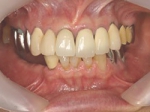

インセラム(オールセラミック)症例②

治療前治療前術前 治療後治療後術後 歯の尖端の透明感までよく再現できている。